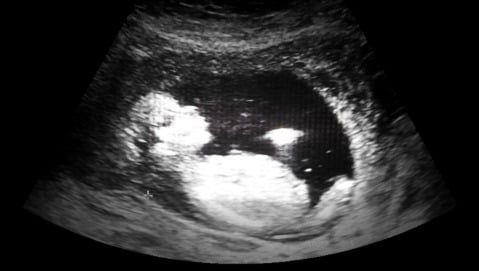

«Spesso la diagnosi è formulata solo quando l’ecografia ha già evidenziato danni al feto - denuncia Giovanni Nigro direttore della Clinica Pediatrica dell’Università dell’Aquila - In questi casi molti ginecologi suggeriscono un’interruzione di gravidanza, senza fare ulteriori approfondimenti».